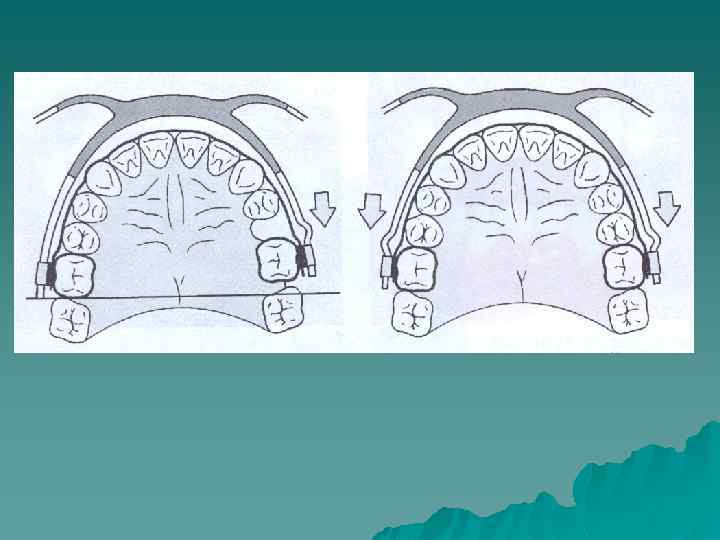

Применение лицевой дуги с шейной тягой. На первые моляры изготавливают кольца с трубками для лицевой дуги. На стороне перемещаемого дистально первого моляра на дуге делают изгиб, который упирается в трубку, а на противоположной стороне конец дуги не имеет упора, и он свободно находится в трубке. В переднем отделе лицевая дуга отстоит от передних зубов. При наложении шейной тяги вся сила лицeвoй дуги направлена на первый моляр, который следует переместить дистально. В случае необходимости дистального перемещения обоих первых моляров на лицевой дуге имеются упоры перед трубками с обеих сторон, и оба зуба будут перемещаться дистально